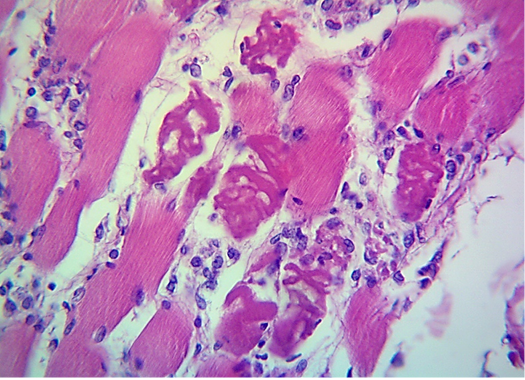

Microscopic image of calf’s’ heart (Tigroid heart appearance) from calf that died from an acute form of FMD, showing myocarditis represented by focal coagulative necrosis of muscle fibers (arrow), with interstitial infiltration of mononuclear inflammatory cells (arrowhead). (H&E, 100x.).

Microscopic image of calf’s’ heart (Tigroid heart appearance) from calf that died from an acute form of FMD, showing focal coagulative necrosis of muscle fibers (arrow) with interstitial infiltration of lymphocytes, plasma cells and histocytes (arrowhead). (H&E, 600x.).